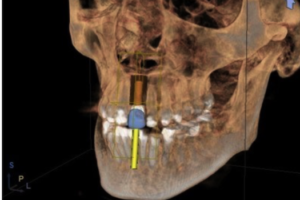

The major component of diagnosis in our office is cone-beam CT (CBCT) analysis, Jaw Tracking, Transcutaneous Electrical Neural Stimulation (TENS), Electromyograph (EMG), and Jaw Joint Sonograph. These instruments have been used for years in medical specialties and are now being used in dentistry to measure postural balance and muscle dysfunction of the jaw, which is the major culprit in the majority of patients reporting headache profiles.